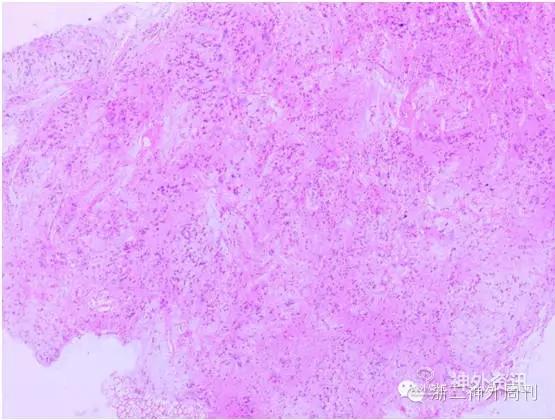

图5. 术后病理显示形态相似的肿瘤细胞聚集成巢状松散地分布在胶质纤维网格中。

室管膜下瘤的病理学特征表现为形态相似的肿瘤细胞聚集成巢状松散地分布在胶质纤维网格中,常见微囊。瘤细胞和细胞核的异型性不明显。